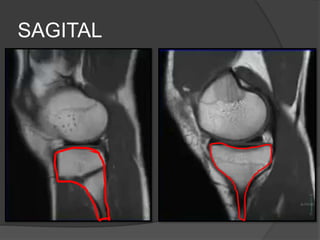

Sagital

 Meniscos

 Ligamentos cruzados

 Cartílago articular

Sagital  Meniscos  Ligamentoscruzados  Cartílago articular